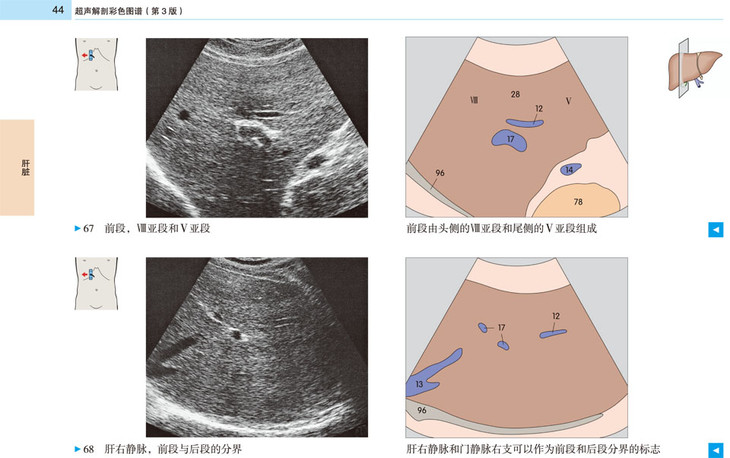

本书提供了全新的、高质量的超声图像和示意图,标示清晰、色彩丰富,为初学者带来极大的帮助。展示了腹部、盆部、甲状腺超声的所有标准切面和扫描路径,标示了各解剖结构和间隙在三维空间的解剖细节及其与超声的关系;并展示了探头定位,以及生成的截面图像、解剖结构、扫描平面在器官中的位置。本书作为优秀的初学者向导,适用于医学生、超声科医师、临床各科医师。